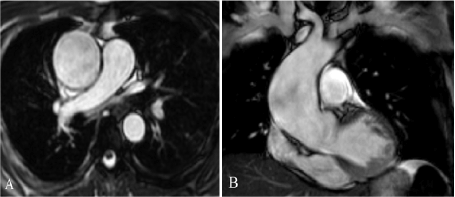

The patient underwent ECG- synchronized MRI examination of the aorta and heart. The study was performed on MRI 1.5T with a specialized cardiac coil [3].

We used T2, T1 weighted scans without and then with T1 weighted scan contrast enhancement. During MRI, we performed contrast enhancement angiography (Figure 1). The maximum diameter of the ascending aorta was 5.4 cm, the distance between proximal and caudal aneurismal edge was 9 cm. The diameter of the aorta before the orifice of the brachiocephalic trunk was up to 3.4 cm, between the orifices of the left common carotid and subclavian arteries - up to 2.4 cm, in the descending part - up to 2.3 cm. The distance from the edge of the brachiocephalic trunk to the cranial aneurismal edge was 5.5cm.

Figure 1. Steady-state free-precession (SSFP) imaging oriented axially (A) and in the coronal plane (B)

To assess the aortic wall's elasticity and contractility, we used a native steady-state free-precession (SSFP) scan mode in the axial and coronary planes (Figure 2).